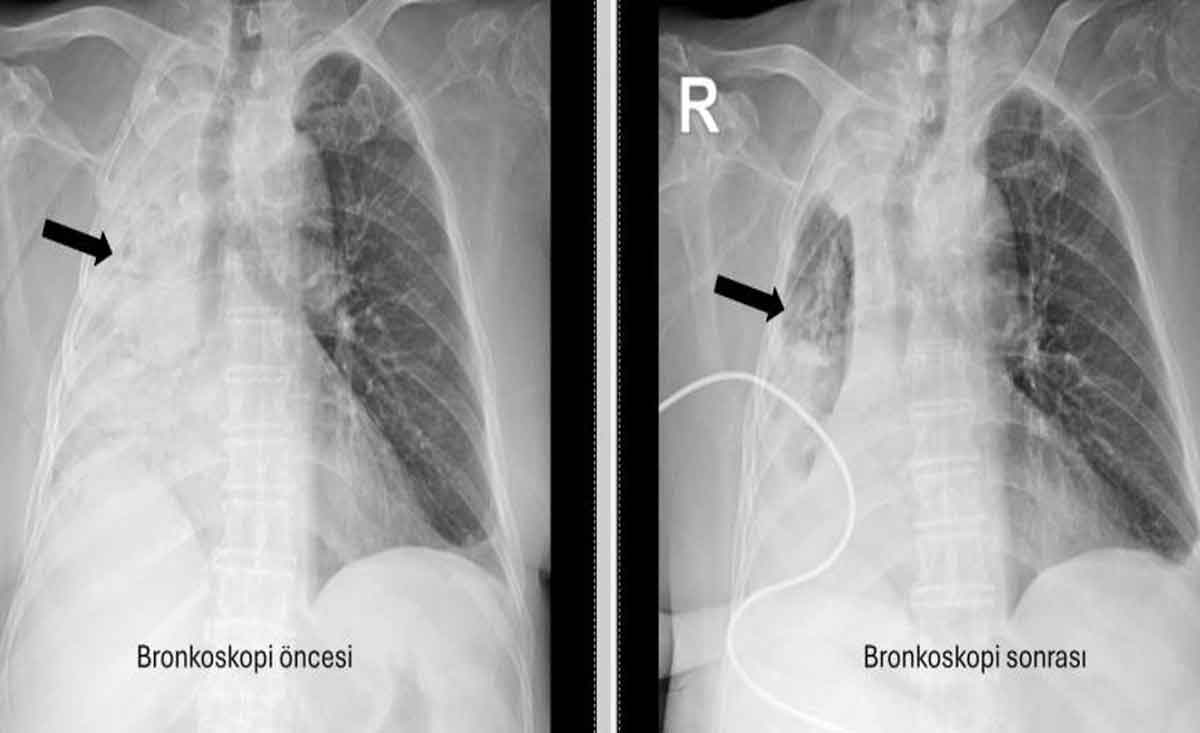

Denizli’de yaşayan ve emekli öğretmen olan 78 yaşındaki felçli kadın son zamanlarda sık sık akciğer enfeksiyonu nedeniyle hastaneye gidiyordu. 1 ay önce gittiği hastanede bronkoskopi yapılmasına rağmen sorun saptanmadığı öğrenildi. Yaşlı kadının son gittiği hastanede sağ akciğerinin tamamen kapandığının tespit edilmesi üzerine Pamukkale Üniversitesi Hastanesine başvuruldu. PAÜ Hastaneleri Göğüs Hastalıkları Anabilim Dalı Öğr. Üyesi Prof. Dr. Göksel Altınışık Ergur, tarafından yapılan tetkiklerde sağ akciğere giden hava yolunun bütünüyle kapalı olduğu görüldü. hastaya acil bronkoskopi planlanıp hemen işlemin gerçekleştirildiğini söyleyen Prof. Dr. Altınışık Ergur, "Fleksibl (esnek, eğilip bükülebilir) bronkoskop ile hava yolları incelenirken çok yoğun ve koyu sekresyon olduğu, bunun iyice temizlenmesi sonucunda ancak hava yollarının incelenebileceği görüldü. Aspiratör (içerideki salgıları emmeye yarayan bir cihaz) sayesinde hava yollarına steril sıvı verilip emilerek bu temizlik yapıldı. Sonrasında sağ akciğere giden hava yolunda sarı bir nesne olduğu görüldü. Bu hâliyle yabancı cisim olduğu anlaşıldığı gibi bunun mısır tanesine benzerliği de açıktı. Yabancı cismi çıkarma işlemi genel anestezi altında, rijit bronkoskop ile yapılmak üzere planlanabilirdi; çünkü bu durumun tedavisi yabancı cismin oradan, ek sorun oluşturmaksızın çıkarmaktı. Ancak, genel anestezi altındaki bir işlem için hastanın genel durumu bozuk olduğundan, özellikle ek hastalıkları ve enfeksiyon varlığı ile işlem riski artacağından hastadaki cismin fark edildiği sırada çıkarılmasına şans vermek daha uygun görüldü. Hava yolu içindeki sıvıları emen aspiratörün gücünü kullanılarak cismin çıkarılması mümkündü. Bronkoskobun ucu, sarı cismin gövdesine dayanıp aspiratör ile emme sayesinde ikisi birbirine sımsıkı yapıştırıldı. Emme gücünün azaltılmamasına dikkat ederek yabancı cisim ve bronkoskop, aynı zamanda hava yollarından dışarıya başarı ile çıkarıldı. İşlem sonrasında hasta yakınına mısır tanesi açısından tıbbi öykü yeniden sorulduğunda, hastamızın bundan beş ay önce yediği pizzanın üzerinde mısır taneleri olduğu öğrenildi. O sırada ani bir yakınma ortaya çıkmadığı için böyle bir ihtimal akla gelmemişti. Düşkün hastalar taneli gıdalar yerken, bu durumun fark edilmeden de gelişebileceğini göstermesi açısından önemli olan bu tablo, hastaların bir dedektif titizliği ile değerlendirilmesi gerekliliğini bir kez daha ortaya koymaktadır" dedi.